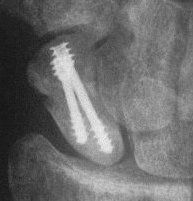

Two screws put in dorsally, LT ligament reinforced with a strip of extensor retinaculum left attached to the triquetrium and anchored into the lunate; temporary capitolunate pin.

Click for larger image

Late, with asymptomatic partial union or nonunion, but no haloing.